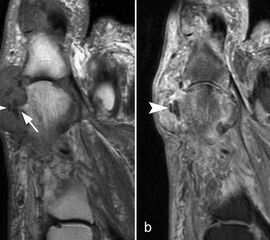

Rupturen ereignen sich am häufigsten an den distalen Insertionen der Metatarsophalan­gealgelenke (Abb. 5), etwas seltener auf Höhe der Metatarsaleköpfchen. Die Läsionen können sehr umschrieben sein, quer durch die gesamte plantare Platte reichen und sich sogar bis in die Kollateralbänder fortsetzen 1. Rupturen der plantaren Platte finden sich am häufigsten an der zweiten Zehe, die dritte Zehe ist etwas seltener betroffen. An der vierten und fünften Zehe sind die Läsionen sehr ungewöhnlich. Rupturen der pantaren Platte führen häufig zu einer ausgeprägten Weichteilreaktion, die nicht als Morton-Neurom fehlgedeutet werden sollte (Abb. 6) und zur Ausbildung einer Neo-Bursa führen können (Abb. 7).

Ein Sonderfall stellt die Großzehe dar: Hier verstärken die Sesambeine, das intersesamoidale und die sesamophalangealen Bänder die Gelenkkapsel. Der faserknorpelige Anteil der plantaren Platte distal der Sesambeine ist oft nur sehr dünn. Verletzungen dieser plantaren Kapselstrukturen des Großzehengrundgelenkes werden auch als „turf toe“ bezeichnet

(Abb. 8).